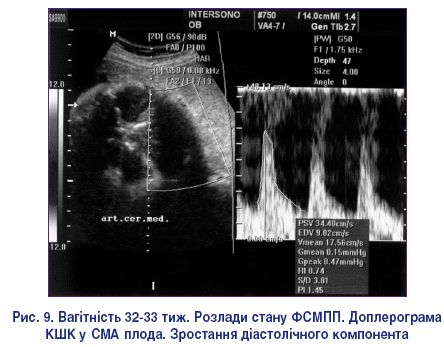

Для проведення доплерометричного контролю гемодинаміки головного мозку плода найбільш оптимальною серед усіх досліджуваних судин вважається середня мозкова артерія плода (СМА), яка має найбільший діаметр, чіткий анатомічний орієнтир розміщення і виражену модуляцію сигналів. Доплерограма у цій судині має вигляд, характерний для судинної системи середньої резистентності – без від’ємних значень діастолічного кровоплину.

При порушенні гомеостазу у ФСМПП у мозкових артеріях плода відбуваються зміни, протилежні змінам кровоплину в аорті і в АП, що являє собою один із компенсаторних механізмів – централізацію кровообігу з переважаючим кровопостачанням життєво важливих органів при наростаючій гіпоксії і розладах метаболізму. Величина діастолічного кровоплину у церебральних судинах спочатку залишається незмінною, а потім збільшується, що виражається зниженням числових значень ІСО (рис. 9). Значний практичний інтерес викликає наявність нормативних показників мозкового кровообігу на фоні вираженого зниження плацентарного кровоплину. У цих випадках зміна патологічних значень мозкового кровоплину на нормальні є ознакою декомпенсації і може бути обумовлена серцевою недостатністю і набряком мозку у плода [15].